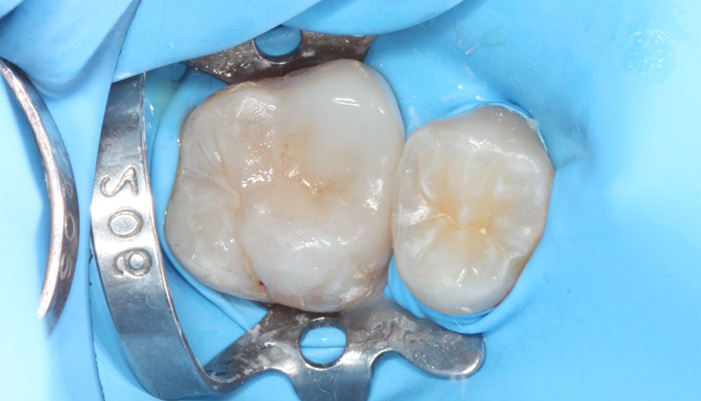

症例3

治療前

治療中

治療の経緯

拡大視野下でむし歯の感染部位を丁寧に確認しながら正確に除去し、歯髄の状態を評価しました。その結果、神経を残せる可能性があると判断し、MTAを用いた歯髄温存療法を選択しました。神経を残すことは、歯の寿命を守ることにもつながります。

| 主訴 | 甘いものや冷たいものがしみる |

|---|---|

| 治療期間 | 1〜3回 |

| 治療費 | ¥33,000 |

| 治療内容 | 深い虫歯に対して歯髄を保護する処置を行い、神経を残す治療を行いました。 |

| 治療のリスク | 虫歯の進行度によっては将来的に神経の治療が必要になる場合があります。 |